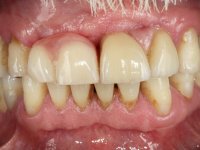

Paciente do sexo masculino, com 64 anos de idade, não fumador, recorreu á minha consulta após traumatismo do sector anterior. Os dentes 2.1 e 2.2 apresentavam extensas fraturas infra ósseas. Os dentes 1.2 e 1.1 apresentavam-se ferulizados com uma resina composta na zona inter-proximal. O dente 1.1 apresentava um tratamento endodôntico sofrível e um poste intra-radicular. O dente 1.2 estava vital e tinha uma extensa restauração da resina composta. Estando ferulizados, não foi possível avaliar o grau de mobilidade dentária de cada um dos dentes, mas o conjunto não tinha mobilidade. Após exame clínico e Imagiológico conclui-se que as raízes dos dentes 2.1 e 2.2 tinham extração indicada. O paciente estava reabilitado provisoriamente com uma prótese removível esquelética com 3 dentes. Apresentava algum comprometimento periodontal e os dentes mostravam as superfícies oclusais e incisais desgastadas. Higiene oral razoável.